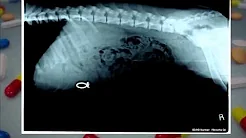

Your Dog Ate What?